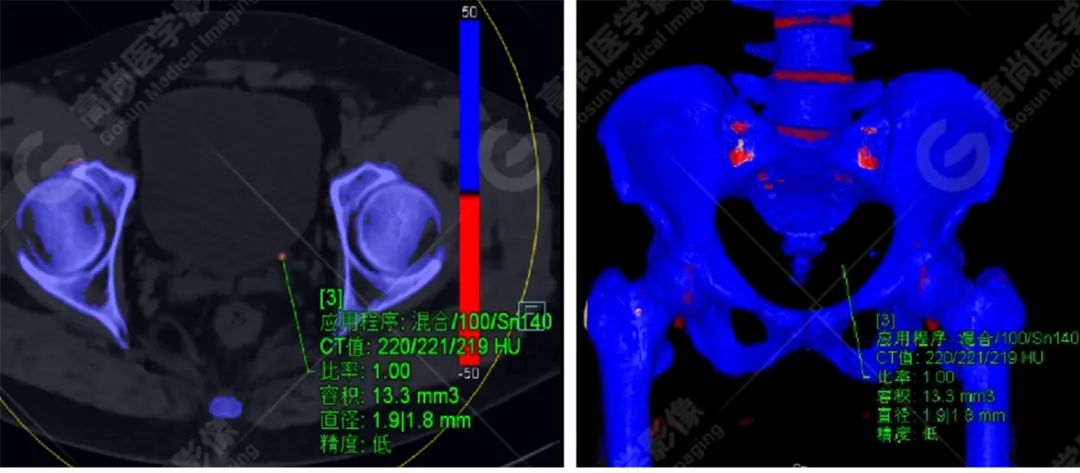

患者左输尿管膀胱入口处小结石,双能量 CT 结石分析示其主要成分为尿酸。

CT 平扫因其安全性和高度敏感性已成为评估泌尿系结石的标准检查方法。而双源 CT(dual-source computed tomography,DSCT)在一次扫描过程中能够同时进行低能量和高能量扫描,使其拥有能够对电子密度相同但光子吸收能力不同的结石进行鉴别的能力。

计算感兴趣区结石在低能量和高能量原位扫描下的衰减值比值(AR 值),与体外结石的已知化学成分的 AR 值进行对比,因此得到体内结石的化学成分。(此步骤在工作站进行,如上成分标识图)

如胱氨酸结石、草酸钙结石及钙磷石,因脆性差,体外冲击波碎石效果不佳,往往需要经皮肾碎石。系统性或者家族性的代谢性结石往往含有某种特定成分,可以通过特异性饮食或者药物来治疗或减少结石的复发,如尿酸结石。

近年来,体外冲击波碎石术(extracorporeal shock wave lithotripsy,ESWL)已成为治疗泌尿系结石的首选方法,不同性质的结石其硬度及易碎程度均有所不同,所选择的冲击波强度亦可进行相应调整,因此 ESWL 前初步识别出结石的成分对于合理调节冲击波能量、减少体外碎石并发症、保护肾功能具有重要意义。